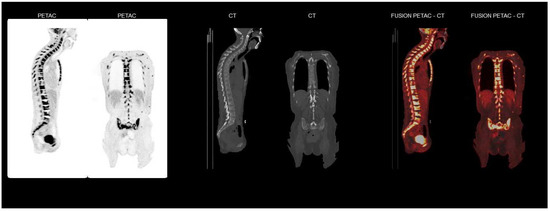

2. Case Report